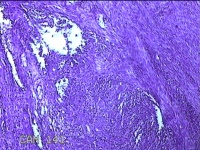

子宫肌瘤

性别

女

年龄

38岁

临床诊断

一般病史

发现子宫肌瘤复发7年余。

标本名称

大体所见

灰白粉红色结节样肿物8.5x5.5x4cm一个,表面糜烂,切面灰白色,编织状,质中。

富于细胞性平滑肌瘤

考虑富细胞平滑肌瘤。

组织处理和染色都不太理想。